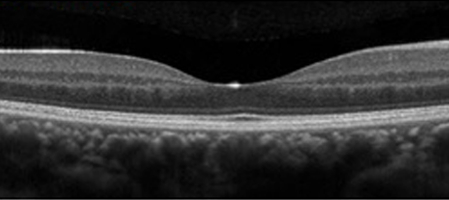

網膜の血管が詰まると、静脈から網膜に血液成分が漏れだし、出血が生じ、網膜の中心である黄斑に水があふれて腫れます。

これを黄斑浮腫と言い、網膜静脈閉塞症の視力低下の原因です。